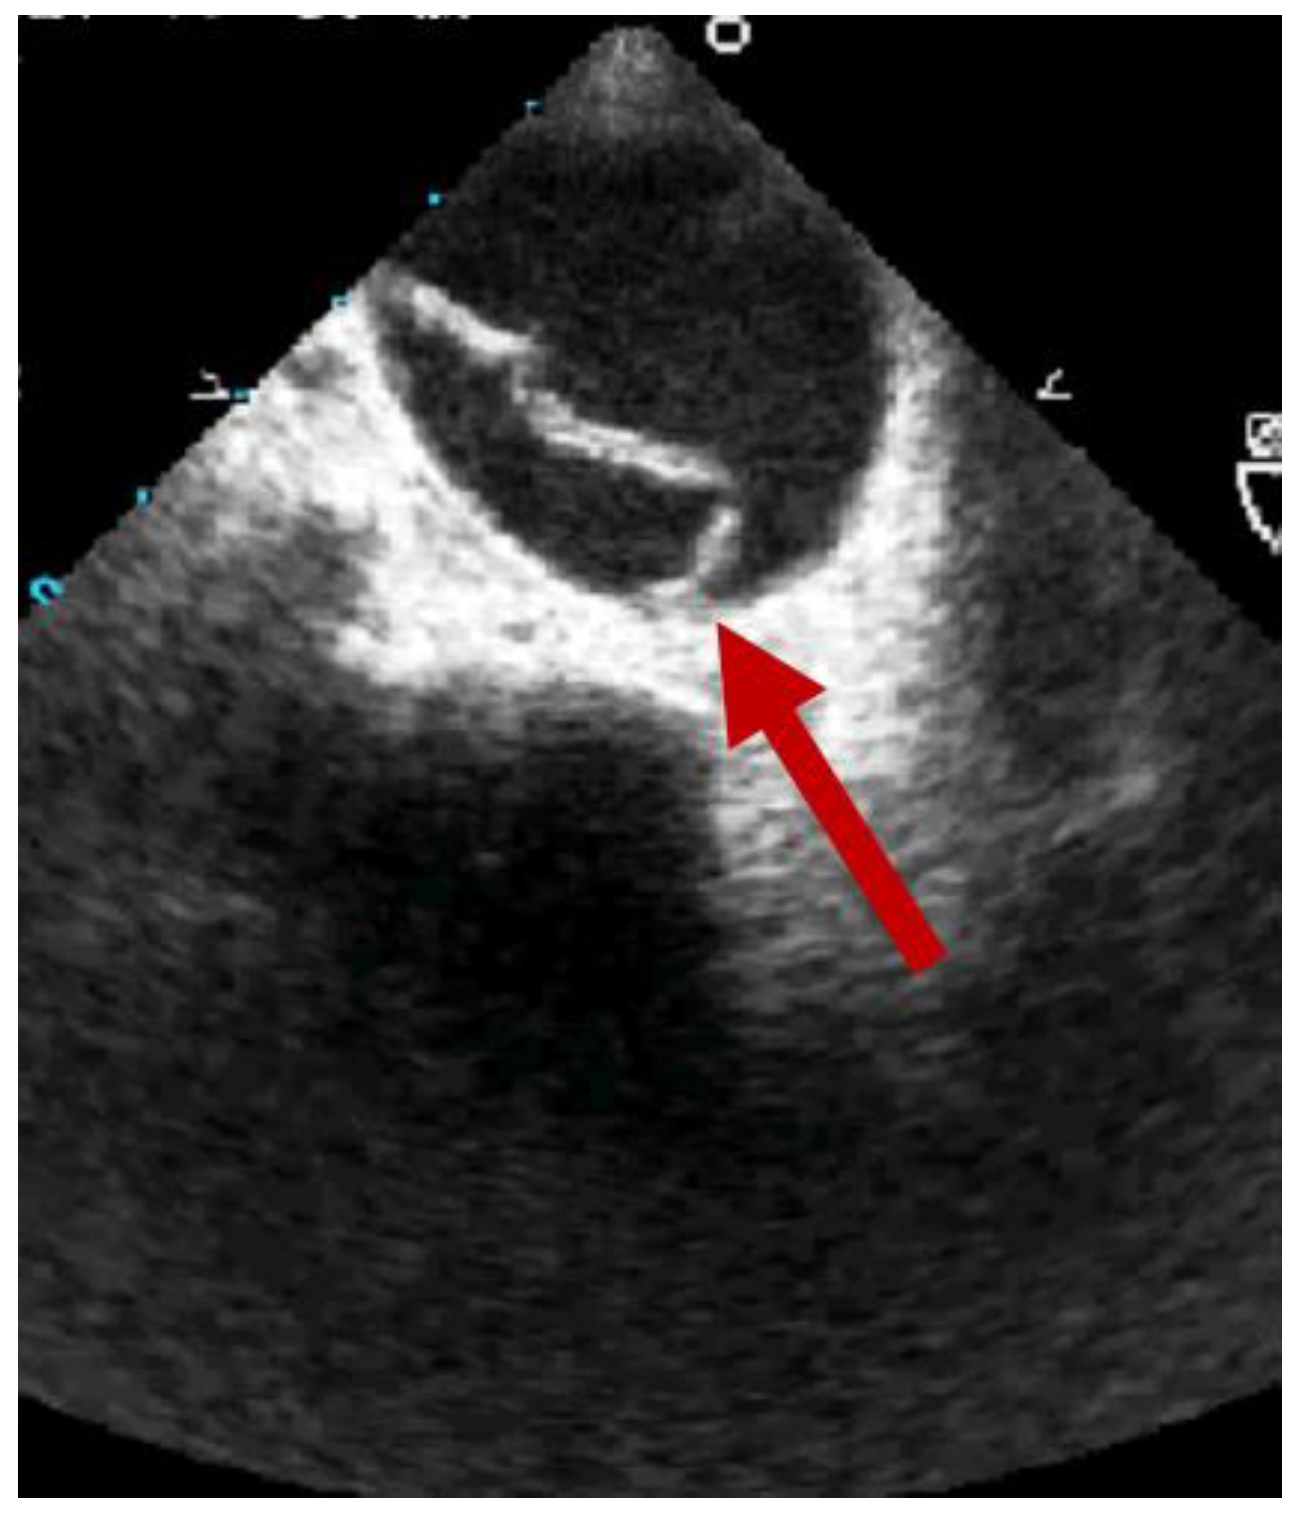

2. Clinical Features of BTAI

3. Diagnosis

- Osman, A.; Fong, C.P.; Wahab, S.F.A.; Panebianco, N.; Teran, F. Transesophageal Echocardiography at the Golden Hour: Identification of Blunt Traumatic Aortic Injuries in the Emergency Department. J. Emerg. Med. 2020, 59, 418–423. [Google Scholar] [CrossRef]

- Cinnella, G.; Dambrosio, M.; Brienza, N.; Tullo, L.; Fiore, T. Transesophageal Echocardiography for Diagnosis of Traumatic Aortic Injury: An Appraisal of the Evidence. J. Trauma Inj. Infect. Crit. Care 2004, 57, 1246–1255. [Google Scholar] [CrossRef]